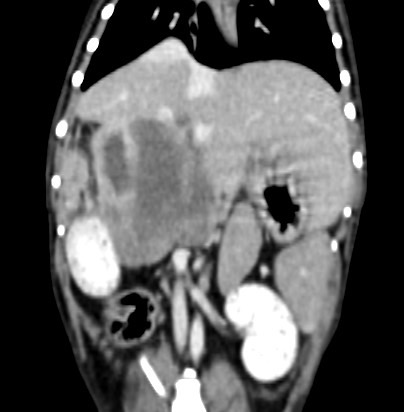

腹腔團塊採樣、術前評估、治療計畫擬定

肝臟團塊,評估範圍、手術可行性、肝臟採樣